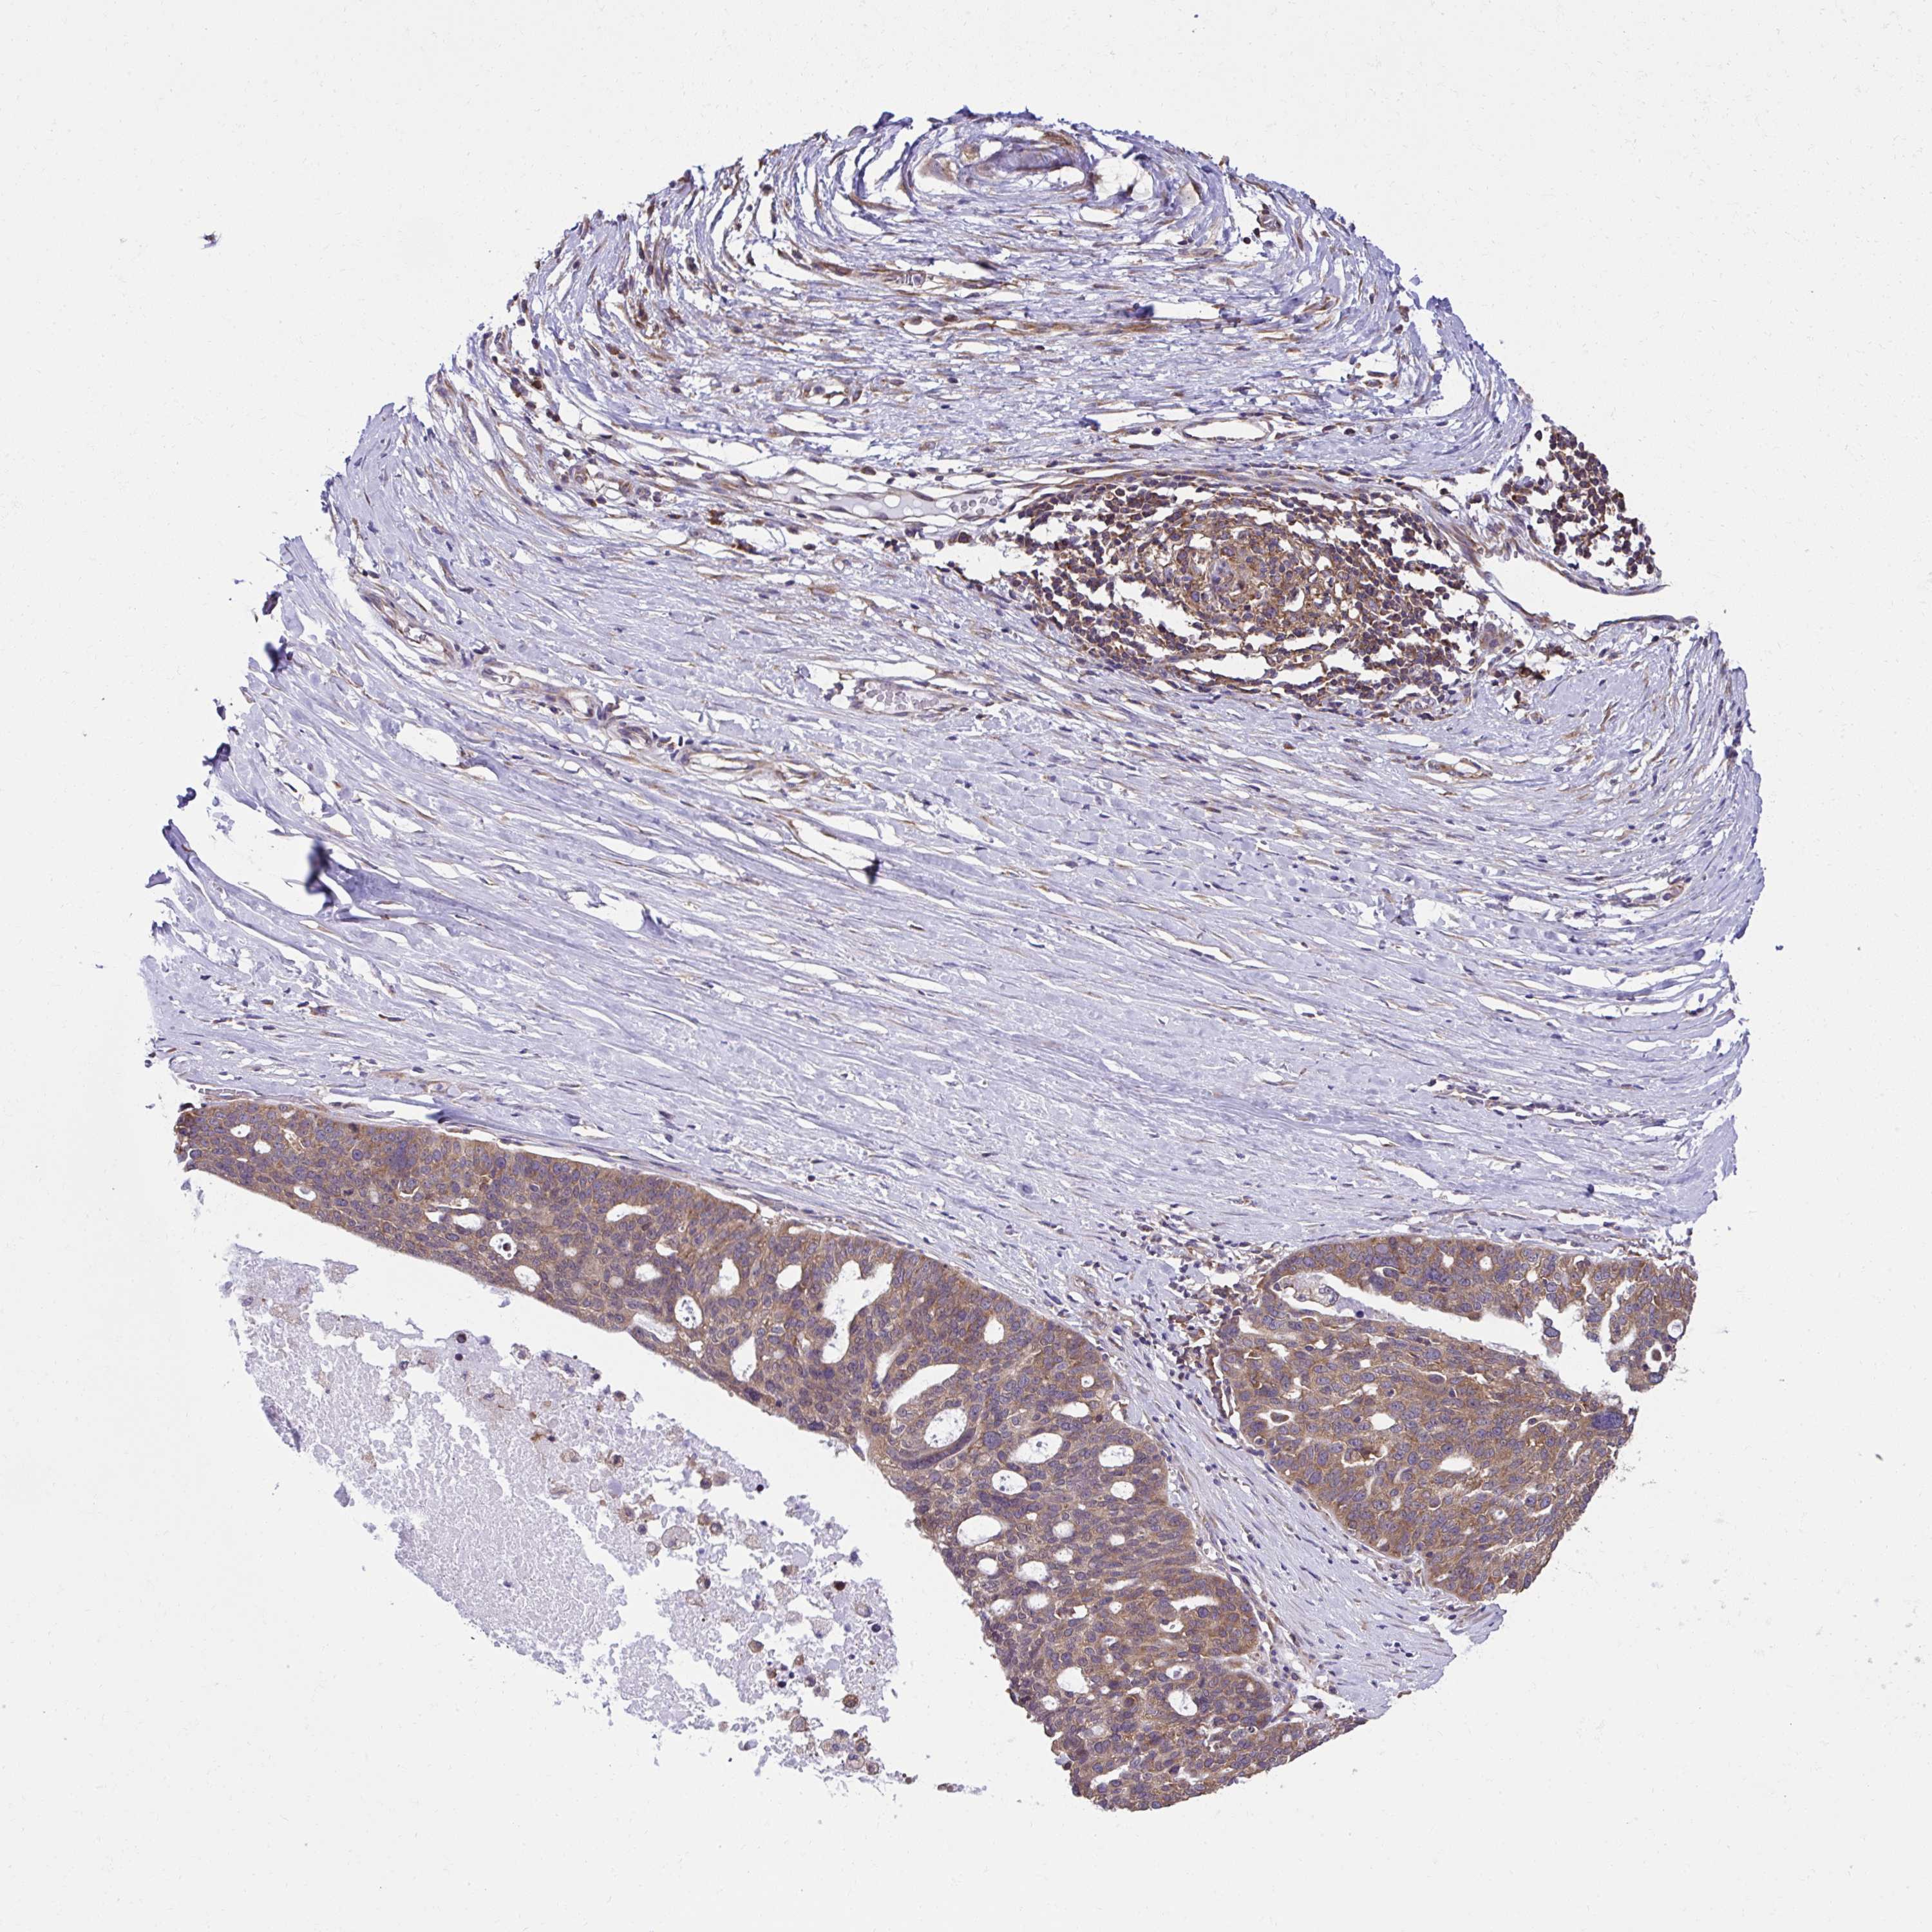

OVARIAN CANCER - Protein expressioni

A mouse-over function shows sample information and annotation data. Click on an image to view it in a full screen mode. Samples can be filtered based on level of antibody staining by selecting one or several of the following categories: high, medium, low and not detected. The assay and annotation is described here.

Note that samples used for immunohistochemistry by the Human Protein Atlas do not correspond to samples in the TCGA dataset.

Antibody stainingi

Antibody staining in the annotated cell types in the current human tissue is reported as not detected, low, medium, or high, based on conventional immunohistochemistry profiling in selected tissues. This score is based on the combination of the staining intensity and fraction of stained cells.

Each image is clickable and will lead to virtual microscopy that enables deeper exploration of all samples and also displays staining intensity scores, fraction scores and subcellular localization as well as patient and tissue information for each sample.

Antibody HPA056586

Staining

High

Medium

Low

Not detected

Intensity

Strong

Moderate

Weak

Negative

Quantity

>75%

75%-25%

<25%

None

Location

Nuclear

Cytoplasmic/membranous

Cytoplasmic/membranous,nuclear

Cystadenocarcinoma, serous, NOS

Carcinoma, endometroid

Cystadenocarcinoma, mucinous, NOS

Carcinoma, NOS